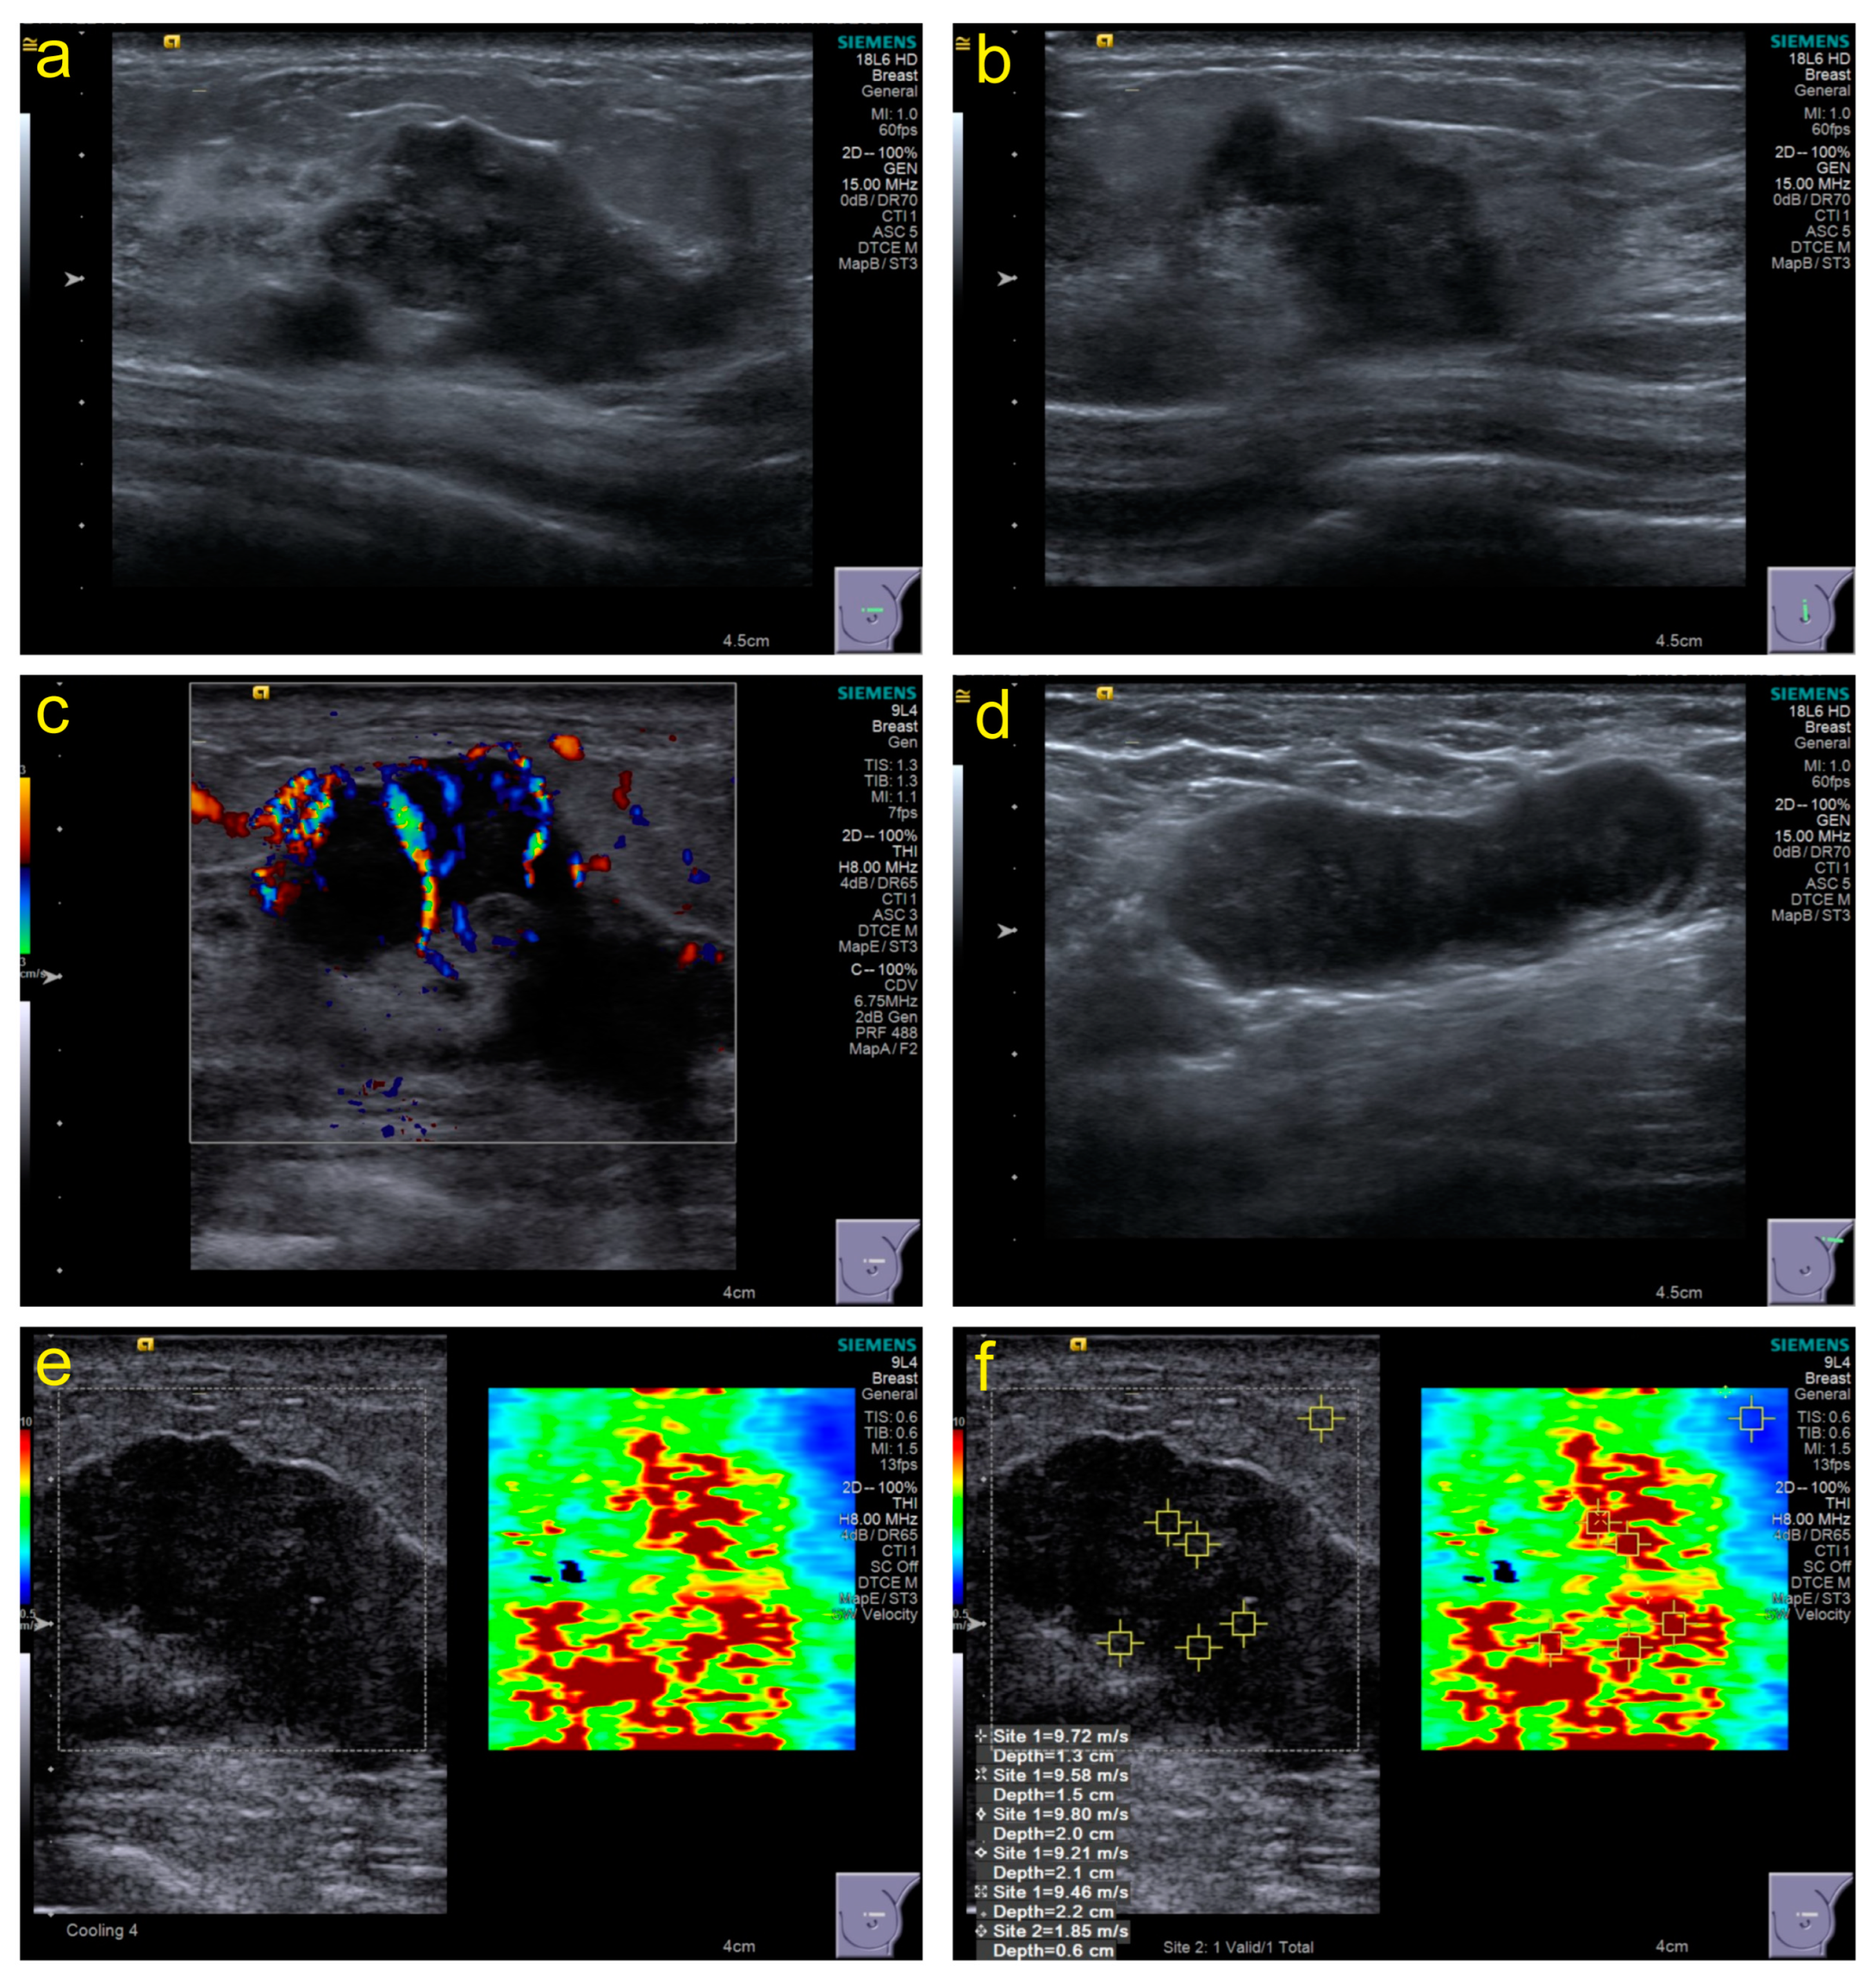

2.2. Conventional US Features

3.2. Conventional US Features

3.3. SWE Parameters